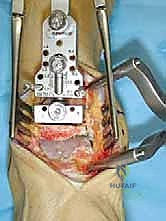

تُجرى العملية عادة تحت التخدير النصفي أو العام، وتستغرق حوالي الساعتين إلى ثلاث ساعات. الدقة هنا تقاس بالمليمترات وأجزاء الدرجة الزاوية.

1. الشق الجراحي والوصول للمفصل

يقوم الجراح بإجراء شق أمامي طولي (Anterior Approach) في منتصف الكاحل. يتم إبعاد الأوتار والأوعية الدموية والأعصاب بعناية فائقة (هنا تتجلى أهمية مهارات الجراحة الدقيقة التي يمتلكها الدكتور هطيف) للوصول إلى محفظة المفصل.

2. إزالة الزوائد العظمية وتحرير المفصل

يتم إزالة النتوءات العظمية (Osteophytes) التي تسبب الألم وتحد من الحركة، وتحرير الأنسجة المتليفة لاستعادة المرونة الأولية للمفصل.